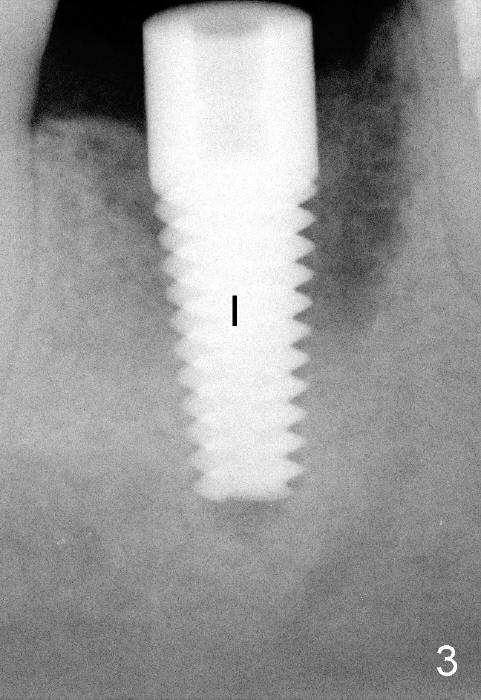

五十多岁的吴先生右下六有根分叉感染(图一),有一次到外地出差疼痛难忍拔除了,一两年后才同意植牙,图二显示已经愈合近远中(M, D)牙槽窝,六乘十七毫米植牙(图三I)好像种得很端正,其实并不完全是这样。让我们回到图二,沿着虚线做个冠状切面,显示右上六号牙以及右下六牙槽骨(图四*),与对侧六号牙冠状切面(图五)对比,右下六牙槽骨往舌侧(L)倾斜(B:颊侧),要植入长而宽的植牙,它就往舌侧倾斜(图八)。为了与对侧牙齿咬合,必须用二十度倾斜的基牙(图六A),但是临床上通过基牙而改变的角度还不够(图七),所以最后牙冠(图十C)不在植牙(I)长轴上,也就是一部分牙冠是悬臂的(*),容易造成陶瓷断裂,基牙松动。避免悬臂牙冠最好的方法便是拔牙后即刻植牙(图九),如果骨质已经吸收,植骨(图十一红色)或者骨扩张时尽量让颊侧骨板往颊侧移动,纠正植牙倾斜角度。